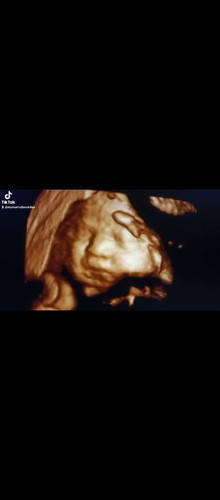

Hallo bun Bunda mau tanya kemarin pada saat saya positif hamil, saya pergi ke dokter untuk USG saya rajin kontrol sampai usia kandungan saya 35 week. Terus hasil pemeriksaan kontrol kemarin saya di suruh balik pada saat usia kandungan saya 37week, tetapi saya di tidak balik ke dokter biasanya. saya cari dokter yang mudah di jangkau (karena dokter kemarin lumayan jauh dari tempat tinggal saya) akhirnya saya cari dokter lain dan kagetnya hasil pemerikasaan USG saya bayi masih berusia 34 week. Sedangkan di aplikasi ini sama di dokter saya sebelumnya usia kandungan bayinya tidak jauh berbeda, menurut bunda bagaimana enaknya? Saya bingung karena sudah mulai ada gelaja tanda" lahir seperti (kontraksi perut, sakit bagian pinggang, kadang juga sakit bagian perut bawah, dan di antara betis/paha) tetaoi belum ada bercak darah melainkan hanya lendir beninh atau seperti keputihan gitu. #seriusnanya #bantusharing #pleasehelp

Usia kehamilan hampir 35 minggu

Assalammu'alaikum, Bunda², saya mau tanya. Usia kehamilan berapa minggu perut terlihat turun ya bun? Saya skrg usia 34-35 minggu, perut sudah kelihatan turun. Memang sewaktu usg 3 hari lalu, dokter bilang bayi sudah turun, posisi sudah bagus, kepala dibawah. Tapi belum masuk panggul. Adakah bunda² dsni sama seperti saya? Usia 37 minggu saya sudah dibolehkan lahiran sama dokter, karena saya hamil dgn ikat mulut rahim. Boleh sharingnya ya bunda²#bantusharing #ingintahu